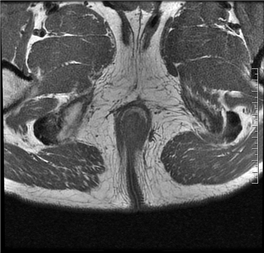

磁共振(MRI)检查的目的是为了判断内口、外口的位置、数目;瘘管走形、瘘管与括约肌复合体之间的关系;判断是否合并脓肿;寻找分支瘘管或窦道;判断活动性与非活动性,从而为临床诊断与治疗规划提供重要参考。

(MRI影像示意图,展示肛瘘常见表现)

在MRI图像中:

◆ 活动期肛瘘MR常表现为T2WI高信号,增强明显强化;

◆ 寻找内口以T1WI增强序列最佳,其次为T2WI抑脂序列,内口影像表现为括约肌内点状T2WI高信号,明显强化或括约肌受牵拉,括约肌间隙消失;

◆ 直径<1CM为瘘管,瘘道的管径最宽处直径>1CM的局限膨隆为脓肿;

◆ 肛瘘愈合期或慢性期,T2WI常表现为低信号,强化减弱或无强化。